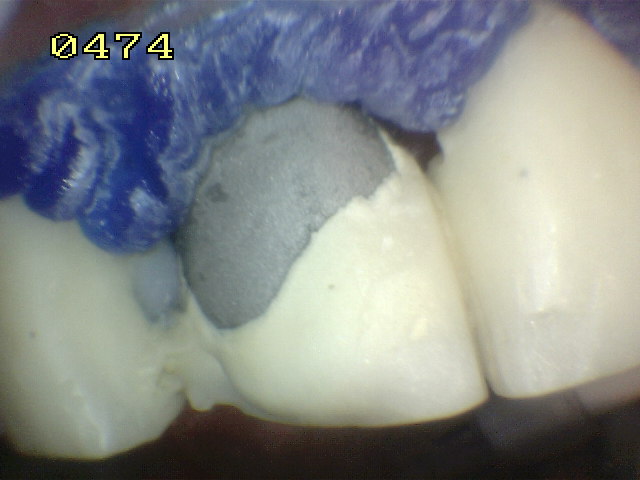

Aspecto del grabado del metal y porcelana Se utilizo silano y adhesivo para resina.  Opacificador de metal   y resina microhibrida A3